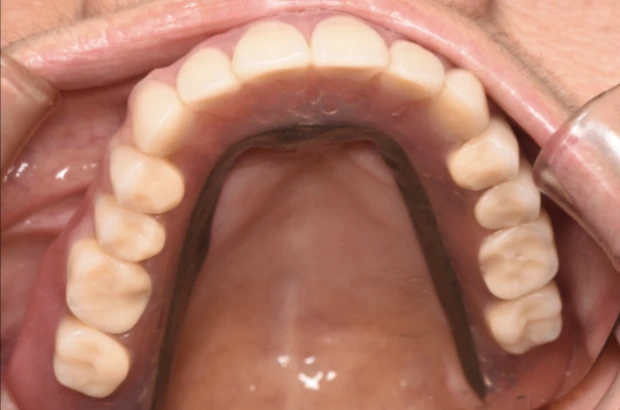

症状を詳しく見る: 症例7

主 訴

何度か入れ歯を作りなおしたが合わない

治療期間

24ヶ月

治療内容

インプラント7本、上顎自費義歯、セラミックCK8本

費 用

3,020,000円